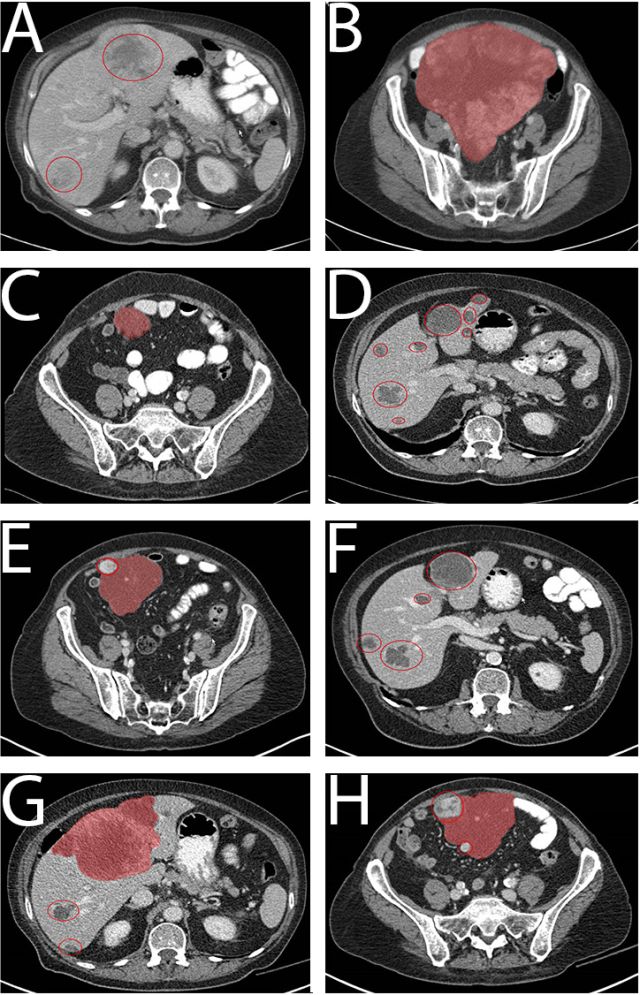

病例1为一个76岁的老年男性,腹部巨大包块(29cm,图1A)),ECOG 3,穿刺证实为GIST,PDGFRα外显子18突变 (NM_006206.5: c.2531_2542del; p.(M844-S847del))。一线给予伊马替尼400mg qd,一周后恶心症状就缓解了,并且生活质量明显改善。治疗持续了1年,最佳疗效为SD(每3月CT评估)。随之腹膜出现了新病灶(图1B),第15个月时调整为二线治疗药物索坦 37.5mg qd。病情在服药后1年内得到良好控制(图1C)。1年后出现PD,中等量腹水(图1D)。经过引流后症状控制,肝脏出现多发转移灶并行穿刺活检,调整为三线药物瑞戈非尼(160mg qd, 3/4方案),PFS为5个月(图1E),并于PD停药后1月死亡(图1F),重头口服伊马替尼无效。患者在三线瑞戈非尼和四线伊马替尼治疗期间留取了血样,发现在1E和1F期间突变拷贝数增加(180-850拷贝/ml,图3A),最后一次随访(死亡前2周)时拷贝数达到4767拷贝/ml。

病例2为76岁的老年女性,因腹痛就诊,CT发现腹腔25cm的肿块伴多发肝转移(图2A和2B),肝穿刺活检提示CD117阳性GIST,突变分析未发现KIT突变,PDGFRα当时未检测。 一线给予伊马替尼400mg qd,10天后临床症状缓解,耐受性良好,3个月后获得PR(图2C 和2D),30个月后原发肿瘤和肝转移灶都出现了PD(图2E和2F)。重头分析原来标本的PDGFRα发现外显子18突变 (NM_006206.5: c.2527_2538del; p.(I843_ D846del))。患者接受了增量的伊马替尼(400mg BID),耐受性良好,但未获得疗效 (3个月后的CT评估,如图2G和2H)。随后调整为索坦37.5mg qd,但2个月后症状持续恶化,OS总共36个月。 由于组织标本采集困难,本例患者进行了血样的ctDNA分析(图3B) ,结果显示患者在伊马替尼治疗的第16.5个月时突变拷贝为6拷贝/ml,这个低水平一直维持到第30个月。在伊马替尼增量开始时为275拷贝/ml,第33个月增长为852拷贝/ml,索坦治疗启动后,一度降至208拷贝/ml,但因患者在第36个月死亡未再收集血样。

PDGFRα激酶结构域活化环的计算机3D模型提示其可以稳定激酶于非活化态势,有利于伊马替尼的结合。而D842V的晶状结构为激酶活化态势,导致ATP亲和力增加,进一步产生耐药(Cancer Chemother Pharmacol. 2011; 67:S25–43. )。图4构建了三种3D模型,分别是PDGFRα-M844_S847缺失、PDGFRα- I843_D846缺失和PDGFRα-D842V(A为D842野生,B-D对应上述突变类型)。通过几何学的空间相互影响分析发现后两种模型对活化没有作用,而且不影响伊马替尼或舒尼替尼与相应的残基结合。

图4. PDGFRα激酶结构域活化环的计算机3D模型